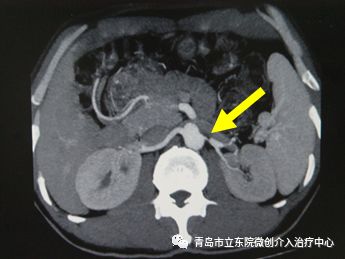

但全面的病因检查又有了新发现。肾动脉CT造影检查发现患者左侧肾动脉有严重狭窄。

贾楠主任根据经验判断,左侧肾动脉重度狭窄是导致患者血压重度升高的根本原因,应进行介入手术治疗。